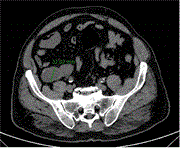

An unusual case of an extensive post-injection retroperitoneal abscess in an intravenous drug user

Georgios Gerasopoulos and others

Journal of Surgical Case Reports, Volume 2024, Issue 6, June 2024, rjae398, https://doi.org/10.1093/jscr/rjae398